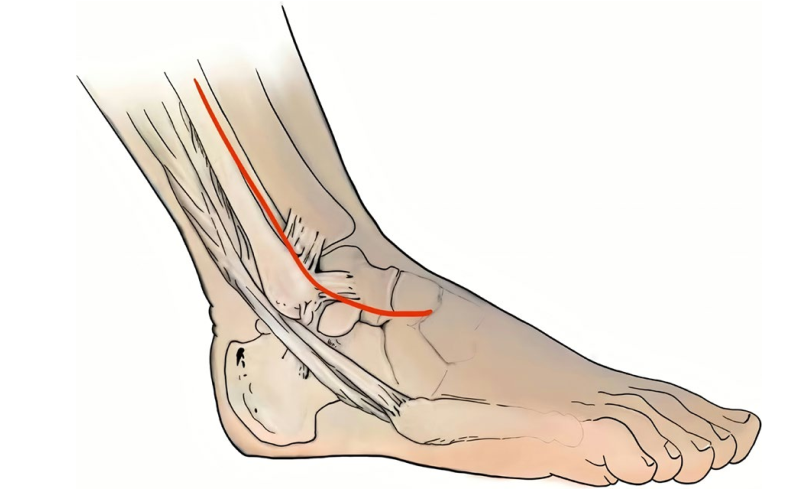

不同于经典的广泛使用的前内侧入路,该方法使用前外侧长切口,自腓骨前缘经外踝至第4跖骨基底,长约15cm。